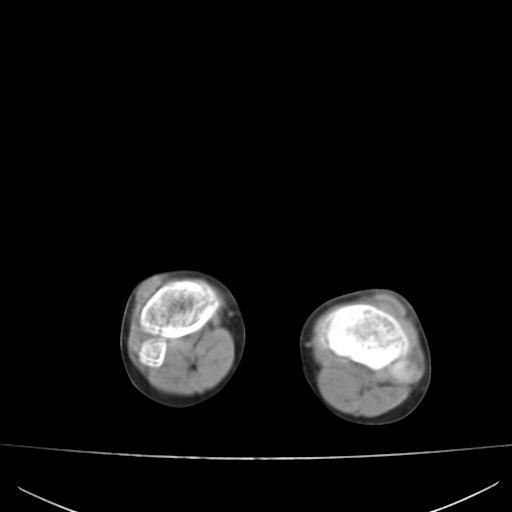

标题: PED0940:M12Y,左股骨下端酸痛畸形 [打印本页]

标题: PED0940:M12Y,左股骨下端酸痛畸形

12岁男孩,左膝关节肿痛8年,近月明显

内生骨软骨瘤?

血友性关节病?